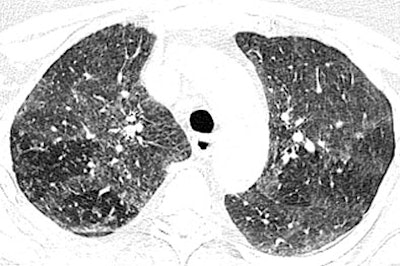

| High-resolution CT images through upper lungs in 53-year-old woman. Above, inspiratory image shows patchy areas of ground-glass attenuation bilaterally with few areas of uninvolved lung. Below, expiratory image shows air trapping in uninvolved areas of upper lungs that is more prominent on right. Images republished with permission of the American Roentgen Ray Society©, from AJR 2007; 188:1050-1053 by Thomas E. Hartmann, Eric Jensen, Henry D. Tazelaar, Viktor Hanak, and Jay H. Ryu. |

In the new pattern of pulmonary disease known as hot tub lung, "centrilobular nodules and areas of ground-glass attenuation are the most common findings, and typically have diffuse but patchy distribution throughout both lungs," Hartman and colleagues wrote. Expiratory images showed evidence of air trapping in all seven cases for which they were available, they added.